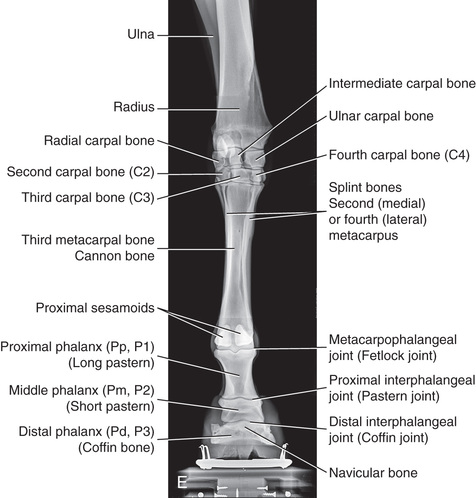

Compare the large-animal anatomy with human and small-animal anatomy (Fig. 24.1). The technical terms are similar but common terms differ.